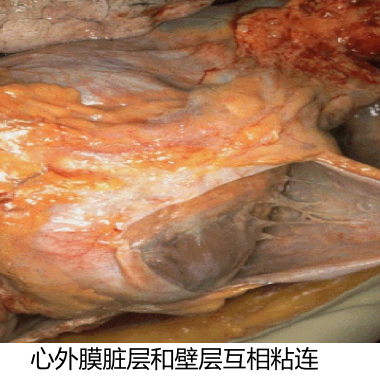

当纤维素性炎发生于浆膜和肺时,少量纤维素渗出,可溶解吸收;多量纤维素渗出则容易发生机化,甚至浆膜腔闭塞,引起器官功能障碍。

如纤维素性心包炎,由于心脏的博动,心包的脏壁两层相互摩擦,使渗出在心包腔内的纤维素在心包膜表面呈绒毛状,称为“绒毛心”。 |

结局:若中性粒细胞渗出较少,释出的蛋白水解酶相对不足,不能将纤维素完全溶解吸收时,可通过肉芽组织的长入而发生机化,最后导致纤维化。发生于胸膜者造成胸膜增厚与粘连,甚至使胸膜腔闭塞。发生于肺者,如大叶性肺炎的灰色肝样变期,肺泡腔内有大量纤维素渗出,使肺实变。

右肺和胸壁之间的粘连 |